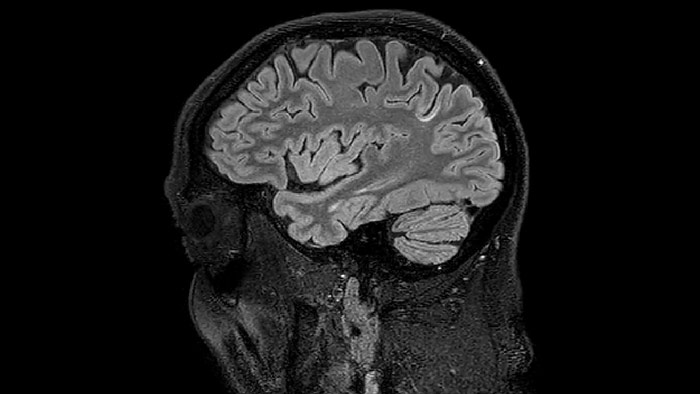

T1 - weighted

Myelin water imaging - T1 weighted

Myelin water imaging (echo 1)

Myelin water imaging with SENSE

Myelin water imaging with Compressed SENSE

With SENSE

With Compressed SENSE

Acquired resolution:

1 x 2 x 5 mm3

1.5 x 2 x 3 mm3

Number of echoes:

32 or 48

56

Echo spacing:

10 ms or 8 ms

7 ms

T1 - Weighted, Myelin Water Fraction Superimposed

MWI Spinal cord coverage

Spinal cord coverage

MWI Smaller, more isotropic voxels

Smaller, more isotropic voxels

MWI Excellent detail in quantitative maps

Excellent detail in quantitative maps

Images courtesy of Adam Dvorak, Department of Physics and Astronomy, University of British Columbia

20%

Myelin water fraction

0%